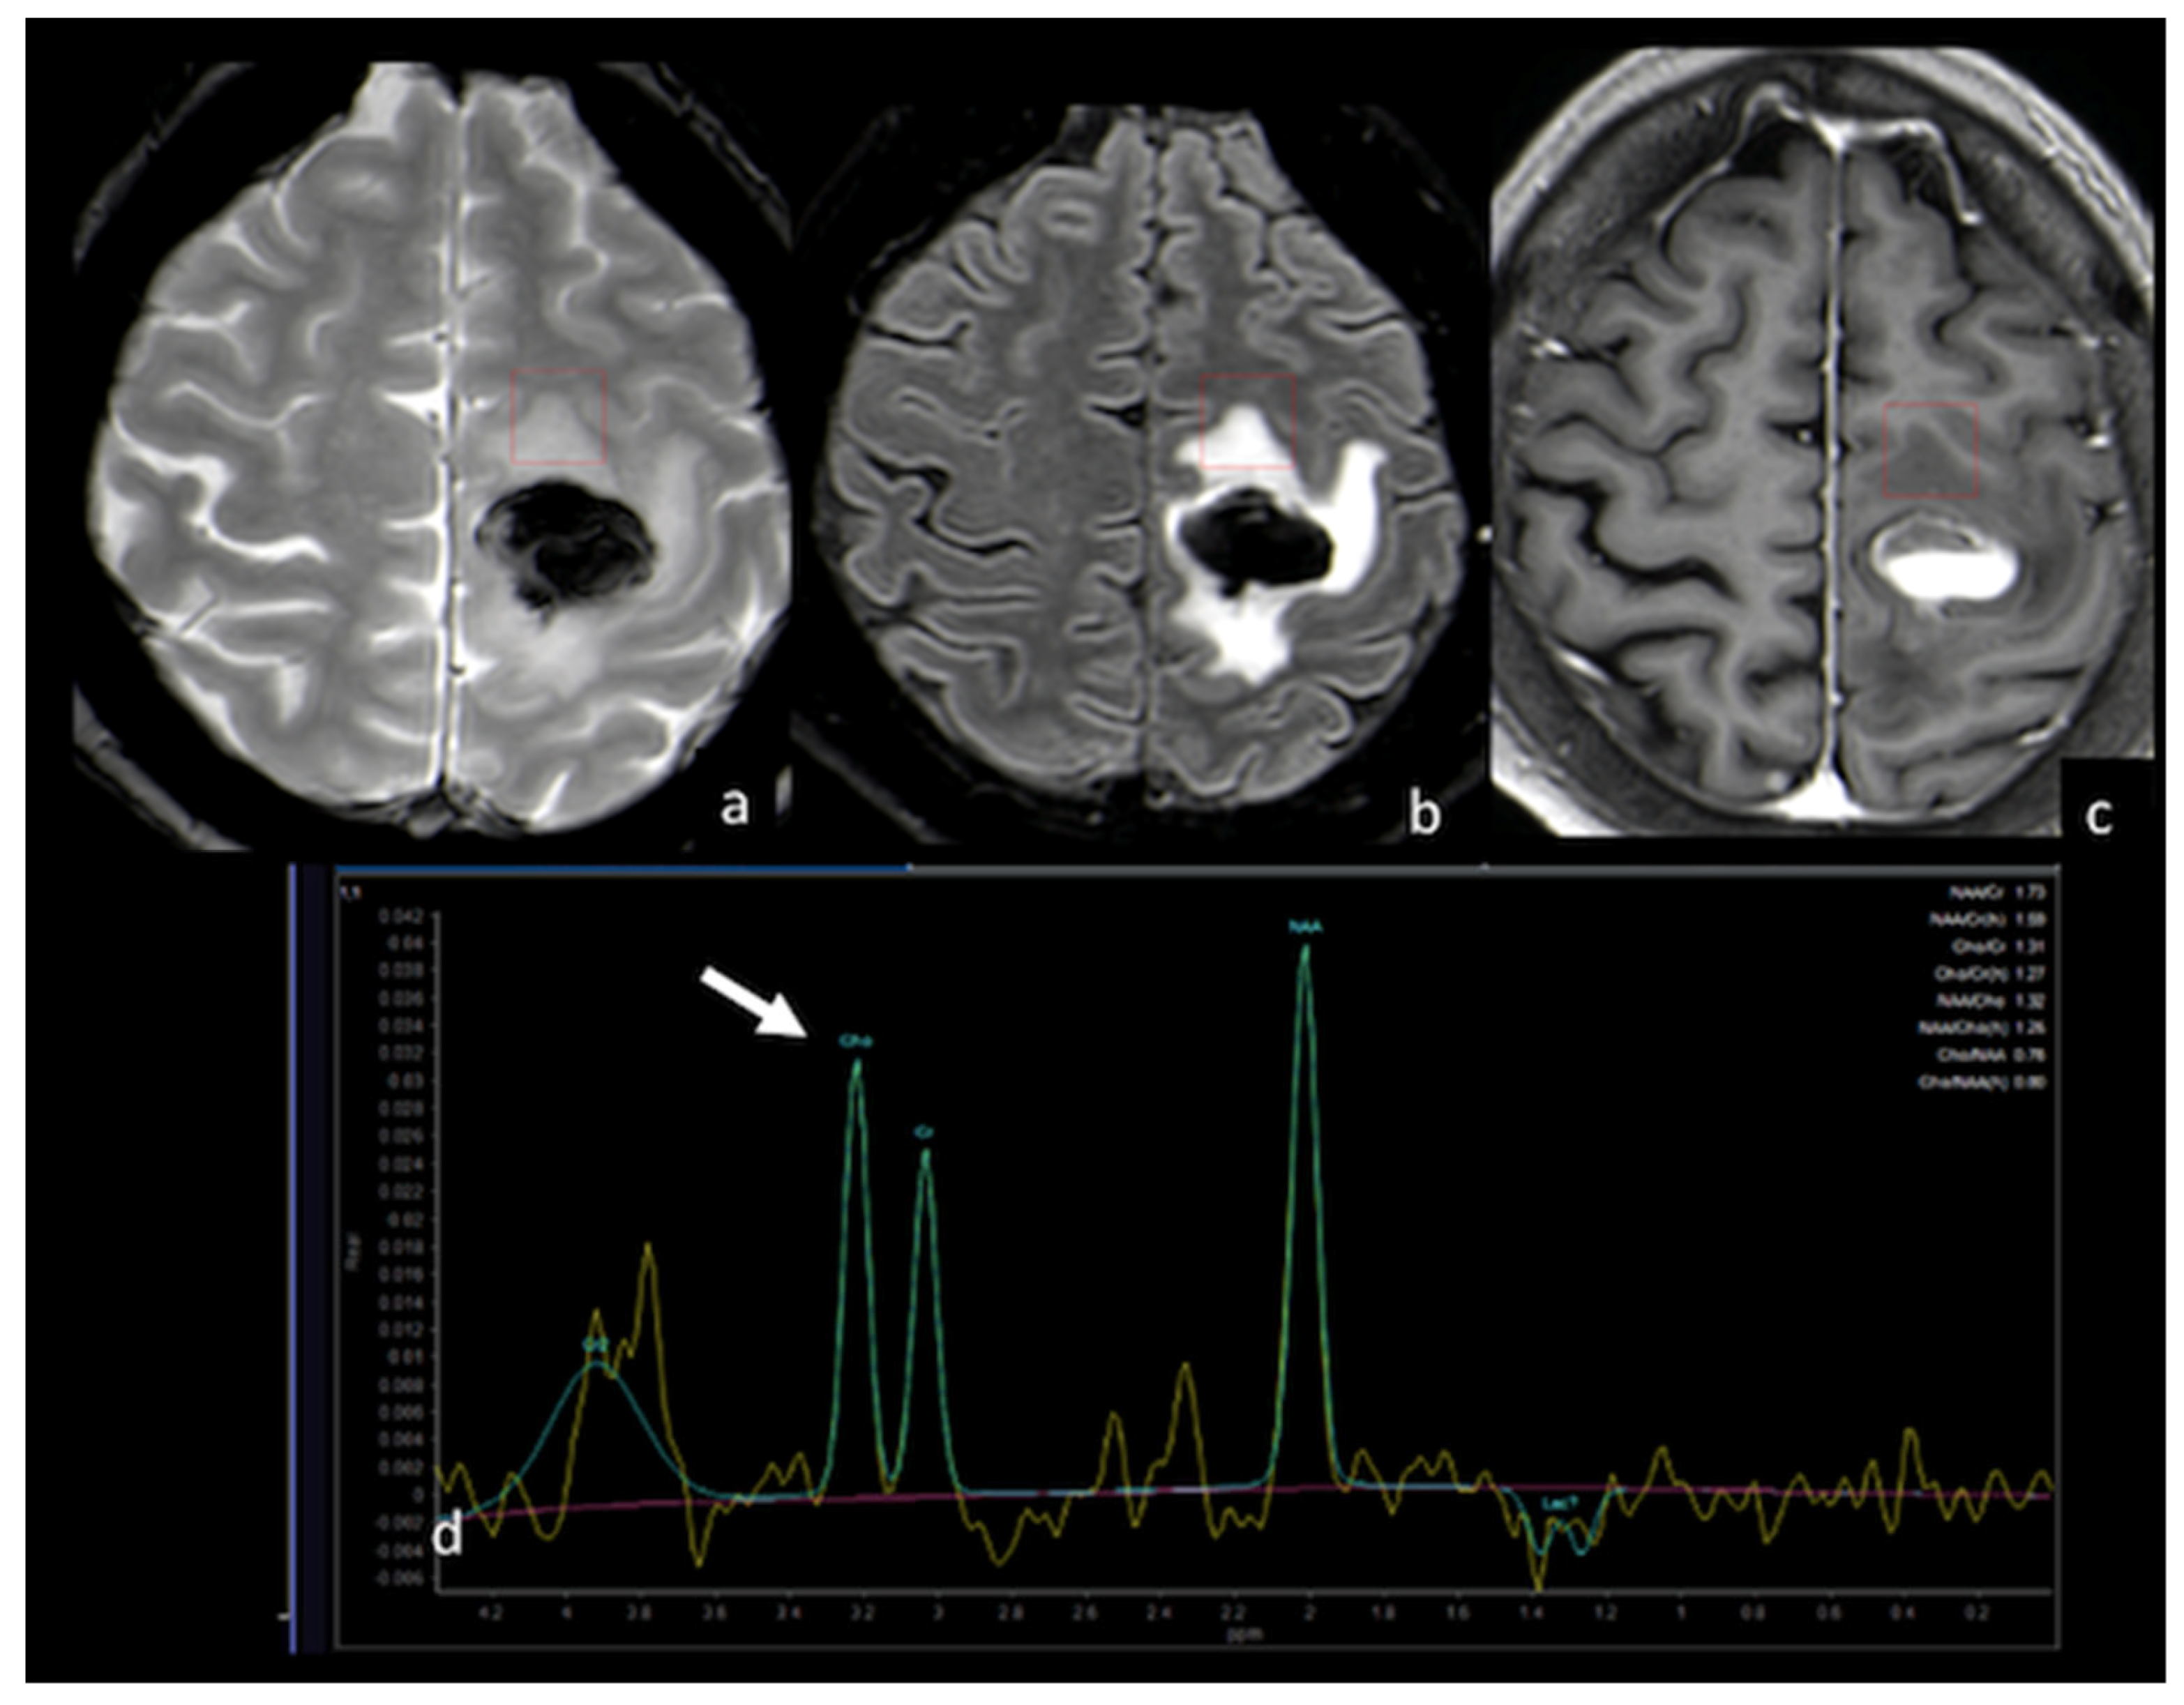

- Chiang, I.C.; Kuo, Y.T.; Lu, C.Y.; Yeung, K.W.; Lin, W.C.; Sheu, F.O.; Liu, G.C. Distinction between high-grade gliomas and solitary metastases using peritumoral 3-T magnetic resonance spectroscopy, diffusion, and perfusion imagings. Neuroradiology 2004, 46, 619–627. [Google Scholar] [CrossRef] [PubMed]

- Bendini, M.; Marton, E.; Feletti, A.; Rossi, S.; Curtolo, S.; Inches, I.; Ronzon, M.; Longatti, P.; Di Paola, F. Primary and metastatic intraaxial brain tumors: Prospective comparison of multivoxel 2D chemical-shift imaging (CSI) proton MR spectroscopy, perfusion MRI, and histopathological findings in a group of 159 patients. Acta Neurochir. 2011, 153, 403–412. [Google Scholar] [CrossRef] [PubMed]

- Wijnen, J.P.; Idema, A.J.; Stawicki, M.; Lagemaat, M.W.; Wesseling, P.; Wright, A.J.; Scheenen, T.W.; Heerschap, A. Quantitative short echo time 1H MRSI of the peripheral edematous region of human brain tumors in the differentiation between glioblastoma, metastasis, and meningioma. J. Magn. Reson. Imaging 2012, 36, 1072–1082. [Google Scholar] [CrossRef] [PubMed]

- Ricci, R.; Bacci, A.; Tugnoli, V.; Battaglia, S.; Maffei, M.; Agati, R.; Leonardi, M. Metabolic findings on 3T 1H-MR spectroscopy in peritumoral brain edema. AJNR Am. J. Neuroradiol. 2007, 28, 1287–1291. [Google Scholar] [CrossRef]

- Cui, Y.; Zeng, W.; Jiang, H.; Ren, X.; Lin, S.; Fan, Y.; Liu, Y.; Zhao, J. Higher Cho/NAA Ratio in Postoperative Peritumoral Edema Zone Is Associated With Earlier Recurrence of Glioblastoma. Front. Neurol. 2020, 11, 592155. [Google Scholar] [CrossRef] [PubMed]